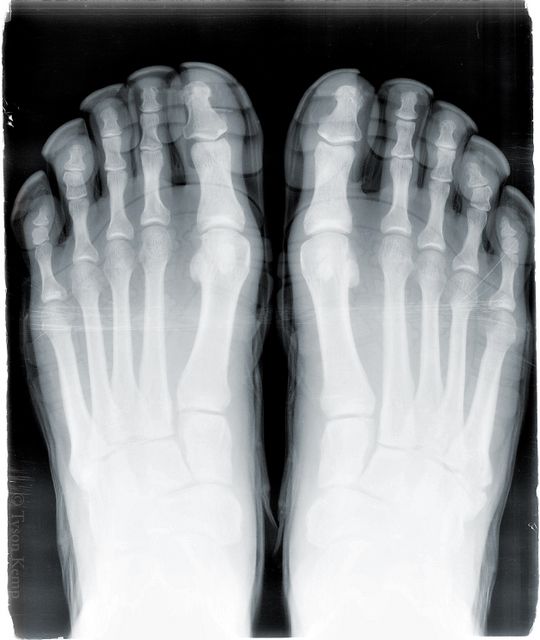

X-Rayed Vibram Five Fingers KSO Treks

Vibram Five Fingers Fan, Tyson, recently went in to have his foot checked and left with an x-ray of his foot. Oh, his foot was still in his KSOs! Tyson gives us the run down:I went in, because I've had pain on the outside of my right foot for some…